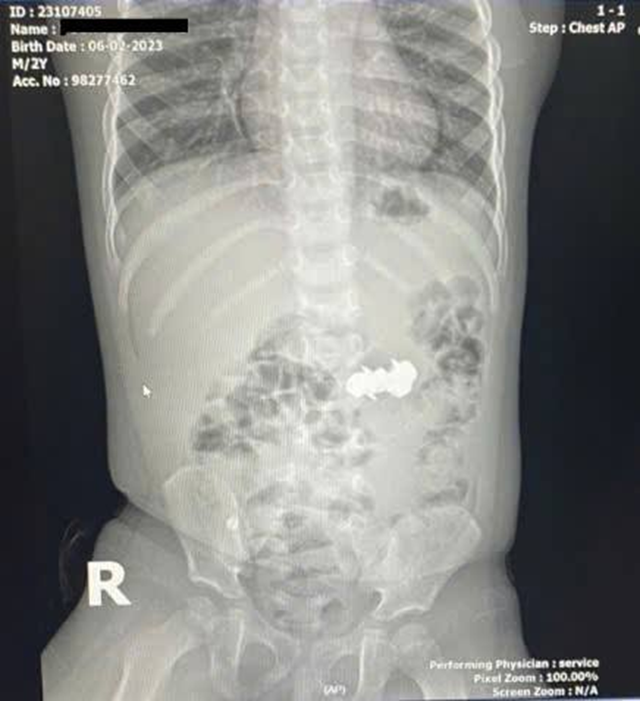

Bé D.H.P. (2 tuổi, trú tại Nghệ An) được gia đình đưa đến viện trong tình trạng nghi ngờ nuốt dị vật trong lúc chơi đồ chơi. Kết quả chụp X-quang bụng cho thấy trong ổ bụng có bốn dị vật kim loại nhỏ hình tròn, có đầu nhọn, nghi là đinh nam châm. Các viên nam châm này đã hút dính nhau trong đường tiêu hoá, tạo nên nguy cơ đặc biệt nghiêm trọng.

Hình ảnh ghi nhận có dị vật cản quang dạng chuỗi nằm ở vùng bụng quanh rốn và hố chậu phải. Các bác sĩ đã hội chẩn liên khoa và thống nhất thực hiện phẫu thuật nội soi ổ bụng cấp cứu.